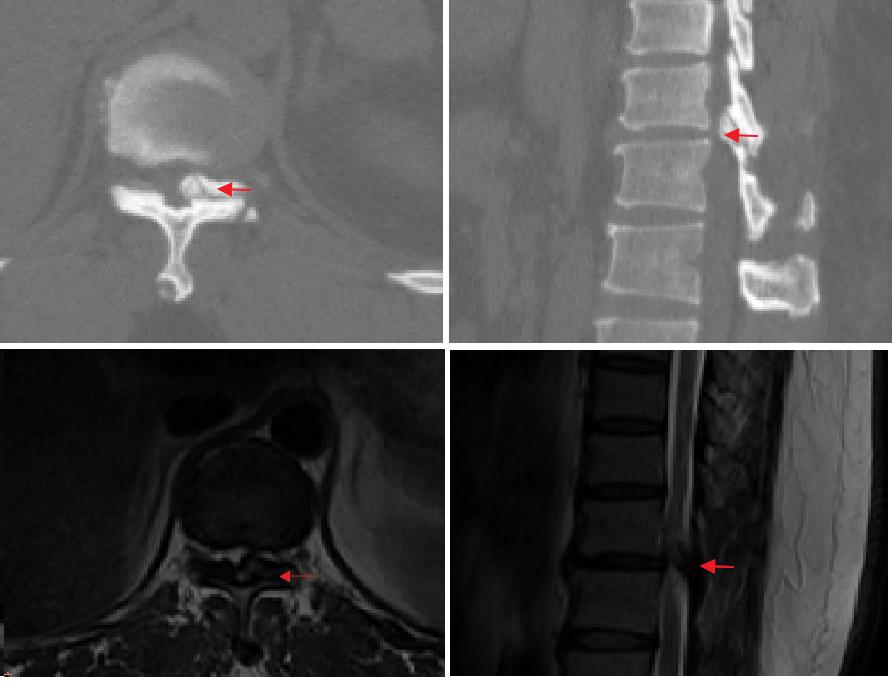

手术患者为一名49岁女性,因半年内双下肢麻木及行走乏力来到北京积水潭医院就诊。经CT和MRI检查显示,患者胸11椎板可见8mm*10mm*3mm的丘状黄韧带骨化灶,导致椎管狭窄,对脊髓产生压迫,该患者被诊断为胸椎黄韧带骨化症。

▲术前影像